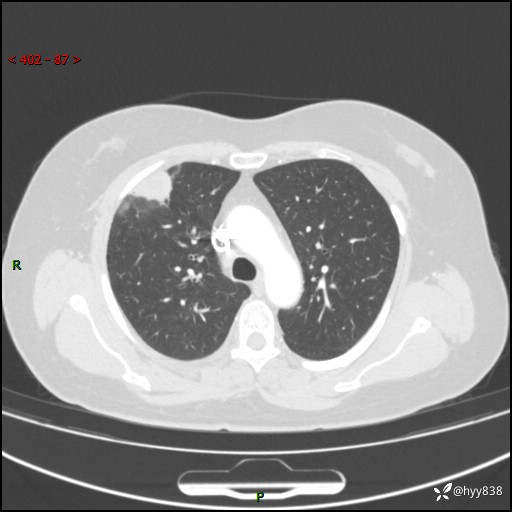

中年女性,间断胸痛2天。“又见”胸膜下团块,性质难定---结果公布~

现病史:患者于2天余前无明显出现间断胸痛,无头痛、头晕,无心慌、胸闷、胸痛、呼吸困难、低热、盗汗,无腹痛、腹胀等不适,未进行进一步诊治。于2024.04.14在当地市人民医院行胸部CT检查提示:右肺上叶胸膜下结节。现患者为求进一步诊治,来我院就诊。以“肺肿物”收入我科。 患者自起病以来,精神可,睡眠可,饮食可,大小便正常,体重无明显改变。

胸部CT增强(肺窗,外院平扫)